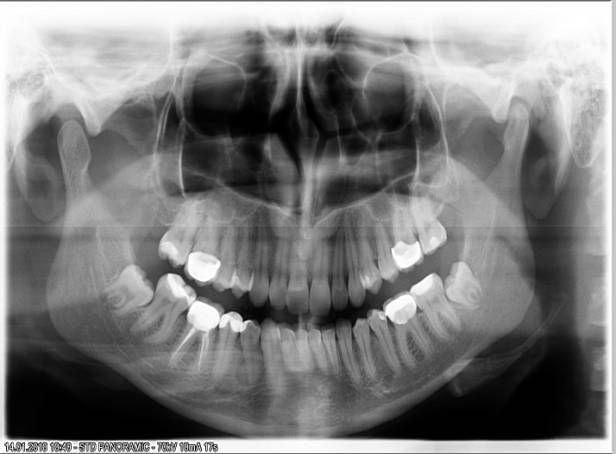

In order to stabilize the height of occlusion after orthodontic treatment the following was recommended: therapeutic rehabilitation in the dentition,

orthodontic treatment, which consisted of a counter-crowns on teeth 16 and 46,

26 and 36, the removal of impacted teeth 48 and 38 (Fig. 2).

Figure 2 Panoramic radiography of patient K after orthodontic and orthopedic

treatment in 2010